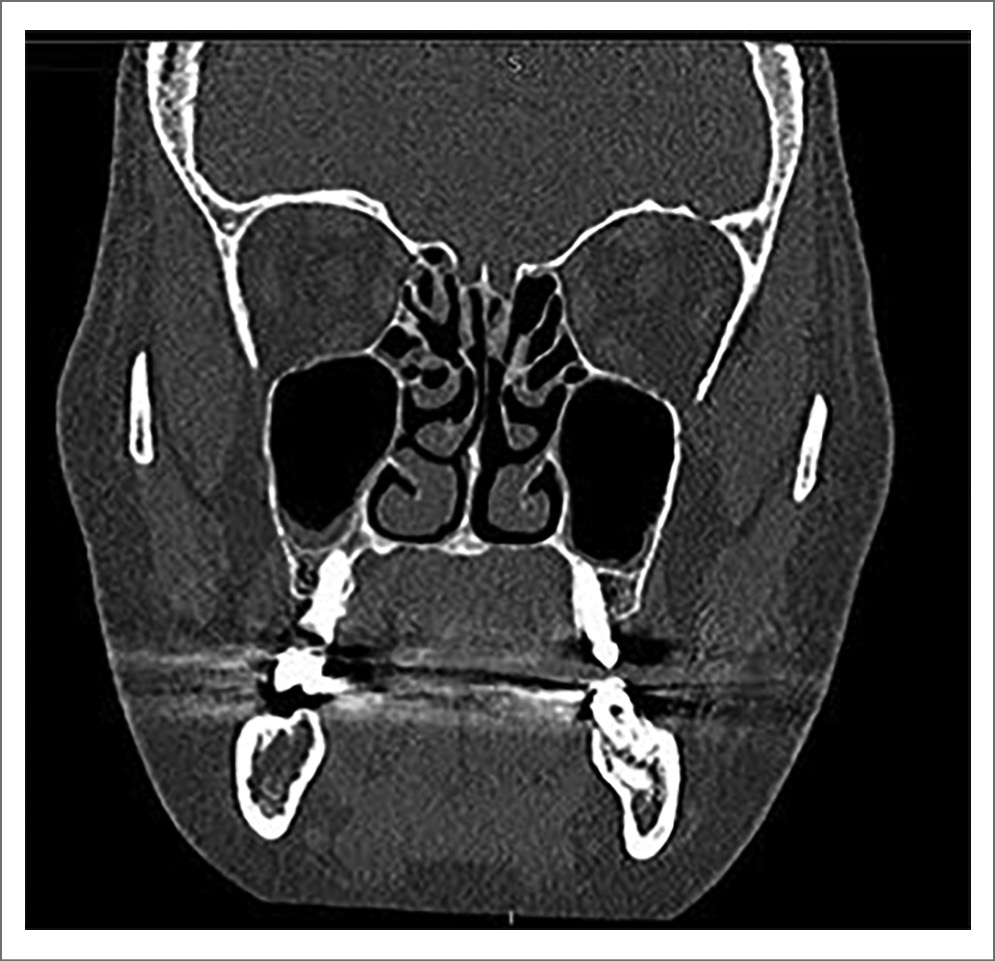

При осмотре: температура тела 36,7°С, артериальное давление 127/81 мм рт. ст., частота пульса 82 уд/мин. Аллергические реакции на лекарственные препараты отрицает. Соматически пациент не отягощен. При ЛОР-осмотре: форма наружного носа не изменена, при перкуссии в проекции левой верхнечелюстной пазухи отмечается болезненность. Слизистая оболочка полости носа умеренно отечна, гиперемирована. Перегородка носа существенно не искривлена, носовые раковины отечны, после анемизации сокращаются. При эндоскопическом исследовании в полости носа отмечается вязкое слизисто-гнойное отделяемое, скапливающееся в среднем и общем носовых ходах с обеих сторон, больше слева. При задней риноскопии – слизистый сгусток в носоглотке. По остальным ЛОР-органам без особенностей. По данным компьютерной томографии околоносовых пазух от 02.04.2022: значительное утолщение слизистой оболочки нижних отделов левой верхнечелюстной пазухи, экссудат в нижней трети правой верхнечелюстной пазухи (рис. 4). Диагноз – «острый двусторонний рецидивирующий верхнечелюстной синусит». Больной трудоспособен.

Рис. 4. Компьютерная томограмма околоносовых пазух пациента Л. до начала лечения.